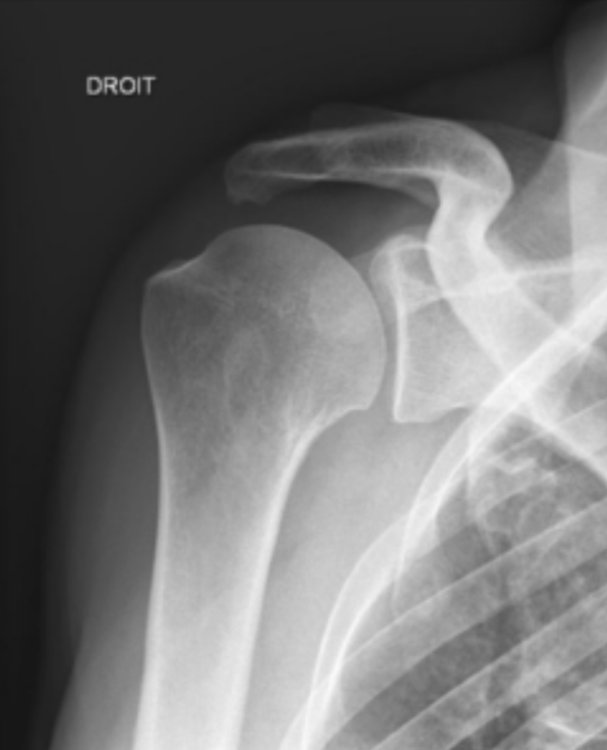

La glène n'est pas orientée en avant et c'est logique : on ne pourrait pas efficacement balancer notre bras vers l'arrière si c'était le cas !

Je te laisse avec une radio d'une épaule normale qui te montre bien que la glène n'est pas orientée en avant car on ne voit pas la cavité de face.